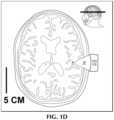

FIG.1D shows the transducer system targeted at a parietal temporal junction.

FIG.1D shows an axial section through a parietal temporal junction area associated with patients with language disturbance associated with Alzheimer's disease (logopenic syndrome).TNS100 may focusultrasonic waves30 attarget area44 in the 2.5 to 3.5 cm range. Apraxic speech localization is more anterior in the frontal operculum. Likewise, more rostral and anterior localizations are used for patients with Parkinson's that have predominant movement disorders including freezing and motor fluctuations (Brodmann area6).